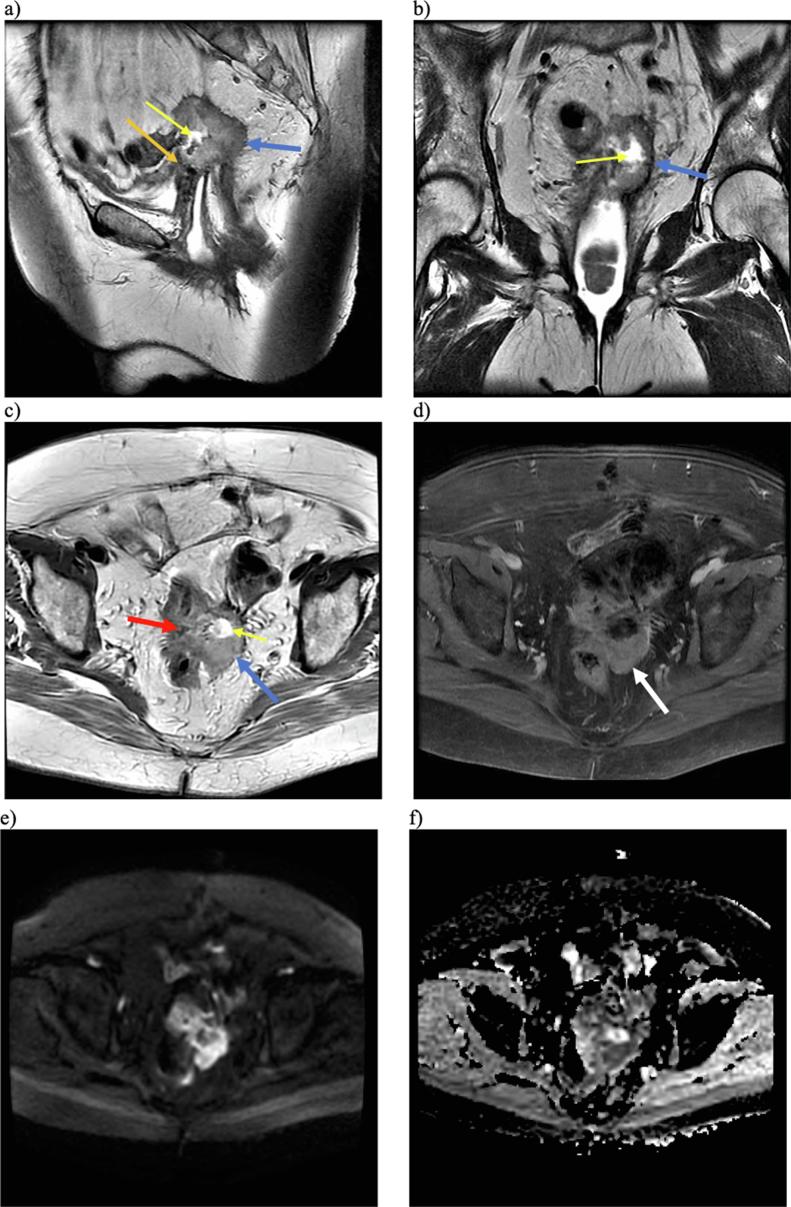

Fig. 3.

Multiplanar, multisequential MRI of the pelvis with T2-weighted sagittal (a), T2 coronal (b), and T2 axial (c) images demonstrating a slightly T2 hyperintense predominantly solid lesion (blue arrows) with central necrosis (yellow arrows) on the vaginal cuff with invasion of the rectosigmoid (red arrow), posterior urinary bladder (orange arrow), and left ureter (not pictured). T1-weighted post-contrast imaging (d) demonstrated enhancement of the solid component (white arrow). Bright signal on DWI (e) and dark signal on ADC (f) sequences is also suggestive of malignancy. (For interpretation of the references to colour in this figure legend, the reader is referred to the web version of this article.)

She was seen regularly for surveillance without notable changes, until 2 years later when she presented with an increase in vaginal discharge and bleeding. The vaginal defect was noted to have enlarged to 1 cm with fatty, friable granulation tissue surrounding the fistula, which demonstrated grade 1 endometrioid adenocarcinoma (Fig. 2). CT scan and MRI revealed a 5.2 cm vaginal cuff mass with central necrosis and invasion into the rectosigmoid colon, posterior bladder, left ureter, and levator (MRI images shown in Fig. 3). PET/CT was also performed and demonstrated significant uptake in the lesion consistent with malignancy (SUV 18.4) (Supplemental Fig. 1). She was discussed at an interdisciplinary tumor board, where the recommendation was made for pelvic exenteration. She underwent an infralevator total pelvic exenteration (no perineal phase required) with colonic conduit for urinary diversion, an end colostomy, omentectomy, and pelvic lymph node sampling. The extenteration specimen showed that the tumor replaced the (ulcerated) vaginal mucosa, invaded the vaginal wall, extended into perivesicular soft tissue, and invaded completely through the rectum. Margins were all negative, and pelvic, obturator, external iliac, and periaortic lymph nodes were benign. The vaginal endometrioid adenocarcinoma was grade 3, stage pT4N0Mx (FIGO stage IVA). She was recommended to undergo surveillance every 3 months for the first 2 years.